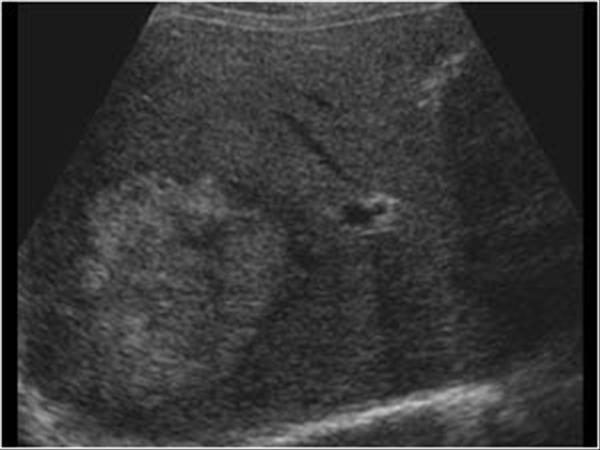

Annular Pancreas

6 year old present

Cystic Fibrosis

autosomal Recessive

Pancreas appears hyperechoic due to microcystic changes, increased fibrotic and fat